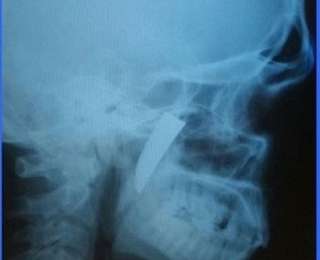

Вашему вниманию очередной случай необычайного везения человека. Во время драки в нёбо мужчины под скуловой дугой зашло лезвие ножа, которое тот обнаружил спустя почти месяц. Лезвие не беспокоило мужчину и обнаружил он его случайно, нащупав что-то постороннее. Наш вам совет, внимательно осматривайте свое тело после любых пусть даже косвенных намеков на попадание в него посторонних предметов, потому как такие ситуации уже не редкость.